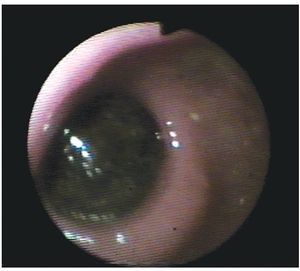

Se trata de paciente femenino de 75 años de edad, la cual acude al servicio de urgencias por presencia de vómitos en varias ocasiones de contenido gástrico, intolerancia a los alimentos, malestar generalizado y datos francos de deshidratación secundaria, con 15 días de evolución desde el inicio de su padecimiento. La paciente tiene antecedentes de diabetes mellitus, hipertensión arterial y refiere gastritis crónica en tratamiento. A su ingreso se encuentra orientada, conciente y sin datos de alarma abdominal, por lo que es internada para su estudio y estabilización con sospecha de cuadro de estenosis péptica pilórica. Se coloca sonda nasogástrica drenando aproximadamente 3 L de material gástrico espeso y restos de alimentos. Laboratorios a su ingreso con hemoglobina de 10 mg/dL, leucocitosis de 13,000 mm3, glucosa 96 mg/dL, urea 30 mg/dL, creatinina 1.8 mg/ dL. Una vez con la paciente en mejores condiciones, se decide realizar panendoscopia encontrando un cálculo biliar gigante impactado en el bulbo duodenal (Imágenes 1 y 2) realizándose múltiples maniobras de extracción con pinzas de cuerpo extraño, las cuales no fueron exitosas. Se realizó ultrasonido demostrando la presencia del cálculo impactado en duodeno, no se apreció dilatación de vías biliares (Imagen 3). Con estos hallazgos se decide someter a la paciente a cirugía, encontrando la presencia de un cálculo biliar gigante dentro del bulbo duodenal con vesícula biliar escleroatrófica, se realiza duodenotomía y extracción del cálculo con duodenorrafia en 2 planos tipo Heineken-Mikulicz sin incidentes transoperatorios (Imágenes 4, 5 y 6) y con adecuada evolución, siendo egresada al octavo día del posoperatorio.

Imagen 4. Duodenotomía y extracción del cálculo biliar.

Imagen 5. Duodenorrafia en 2 planos tipo Heineken-Mickulicz y parche de epiplón.